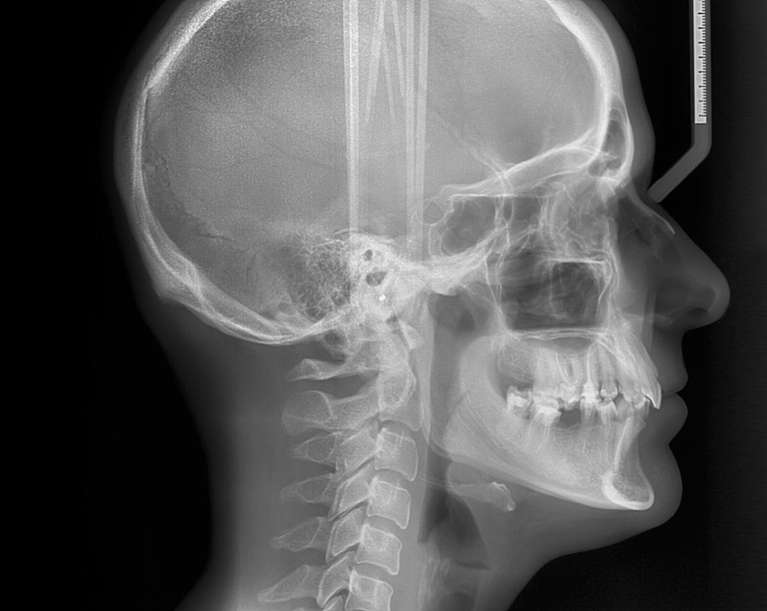

Cephalometric (Ceph) X-Ray

Cephalometric x-rays, or ceph x-rays, provide side-profile views of the head, jaw, and airway. This detailed imaging is commonly used to identify impacted teeth and dental abscesses, plan orthodontic treatment, and diagnose TMJ problems. For children, we commonly use ceph x-rays to monitor oral development and evaluate bite alignment.